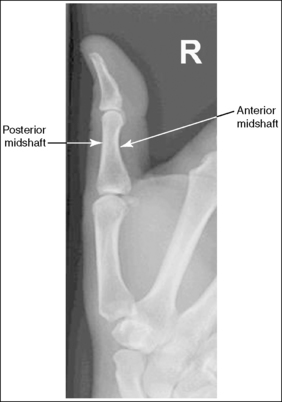

See Figure 4-36 and Box 4-13.

Contrast and density are adequate to demonstrate the pronator fat stripe and surrounding posterior wrist soft tissue.

• The pronator fat stripe is one of the soft tissue structures that should be demonstrated on all lateral wrist projections (Figure 4-37). It is located parallel to the anterior (volar) surface of the distal radius, is normally convex, and lies within 0.25 inch (0.6 cm) of the radial cortex. Bowing or obliteration of this fat stripe may be the only indication of a subtle radial fracture.

The wrist is in a lateral projection. The anterior aspect of the distal scaphoid and pisiform are aligned, and the radius and ulna are superimposed.

• A lateral projection of the wrist is accomplished by flexing the elbow 90 degrees and abducting the humerus until it is parallel with the IR, placing the entire arm on the same horizontal plane. Rotate the wrist into a lateral projection with its ulnar (medial) aspect against the IR (Figure 4-38). To ensure a true lateral projection, place the palmar aspect of your thumb and forefinger against the anterior and posterior aspects, respectively, of the patient's wrist joint, as shown in Figure 4-39. Adjust wrist rotation until your thumb and finger are aligned perpendicular to the IR.

• Detecting wrist rotation. The relationship between the pisiform and distal aspect of the scaphoid can best be used to discern whether a lateral wrist projection has been obtained. On a lateral projection, these two carpals should be superimposed, with their anterior aspects aligned. When the wrist is rotated, the anteroposterior relationship between the distal scaphoid and pisiform changes, and the pronator fat stripe is obscured. If the anterior aspect of the distal scaphoid is positioned posterior to the anterior aspect of the pisiform, the patient's wrist was externally rotated (see Image 45). If the anterior aspect of the distal scaphoid is positioned anterior to the anterior aspect of the pisiform, the patient's wrist was internally rotated (see Images 46 and 47). A second method of determining how to reposition a rotated lateral wrist projection uses the radius and ulna. The ulna is positioned anterior to the radius when the wrist was externally rotated and the ulna is positioned posterior to the radius when the wrist was internally rotated. Because the exact amount of superimposition of the radius and ulna depends on the position of the humerus, and their poor positioning is not as sensitive, you should always view the pisiform and distal scaphoid relationship when determining whether the wrist is in a lateral projection.